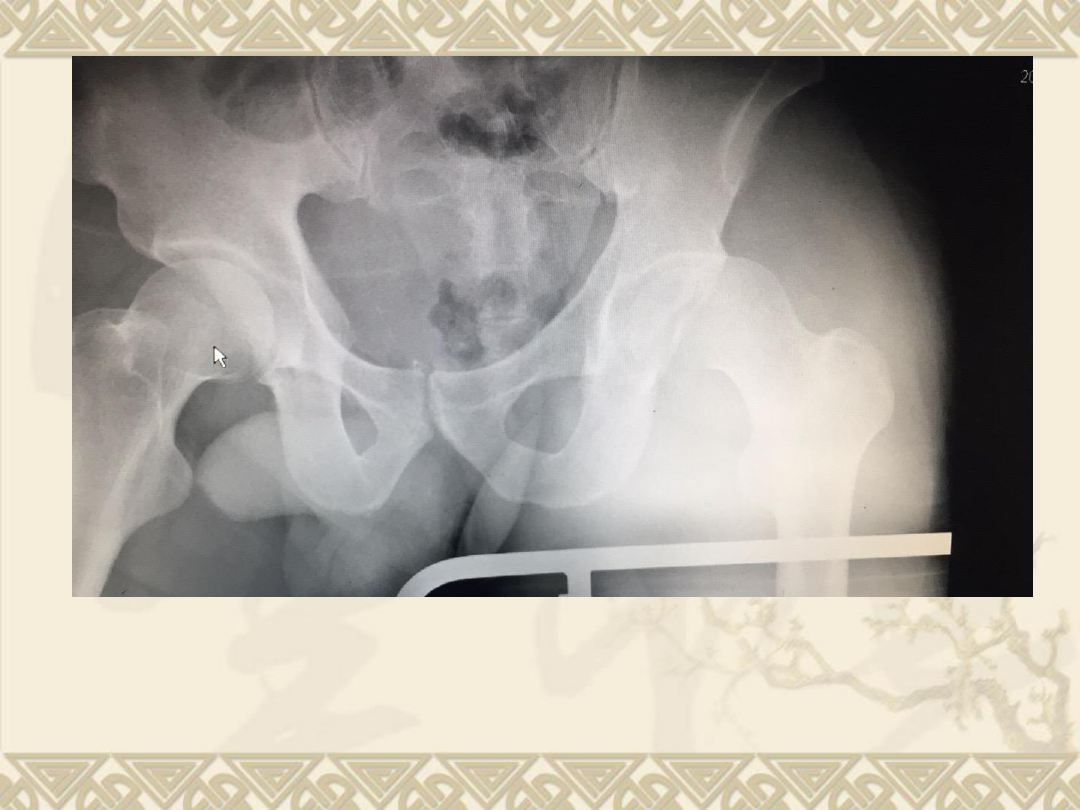

入院后拍片

v

1

、右股骨头骨折(

Pipkin

Ⅳ型骨折)

2

、髋关节后脱位

3

、髋臼后缘骨折